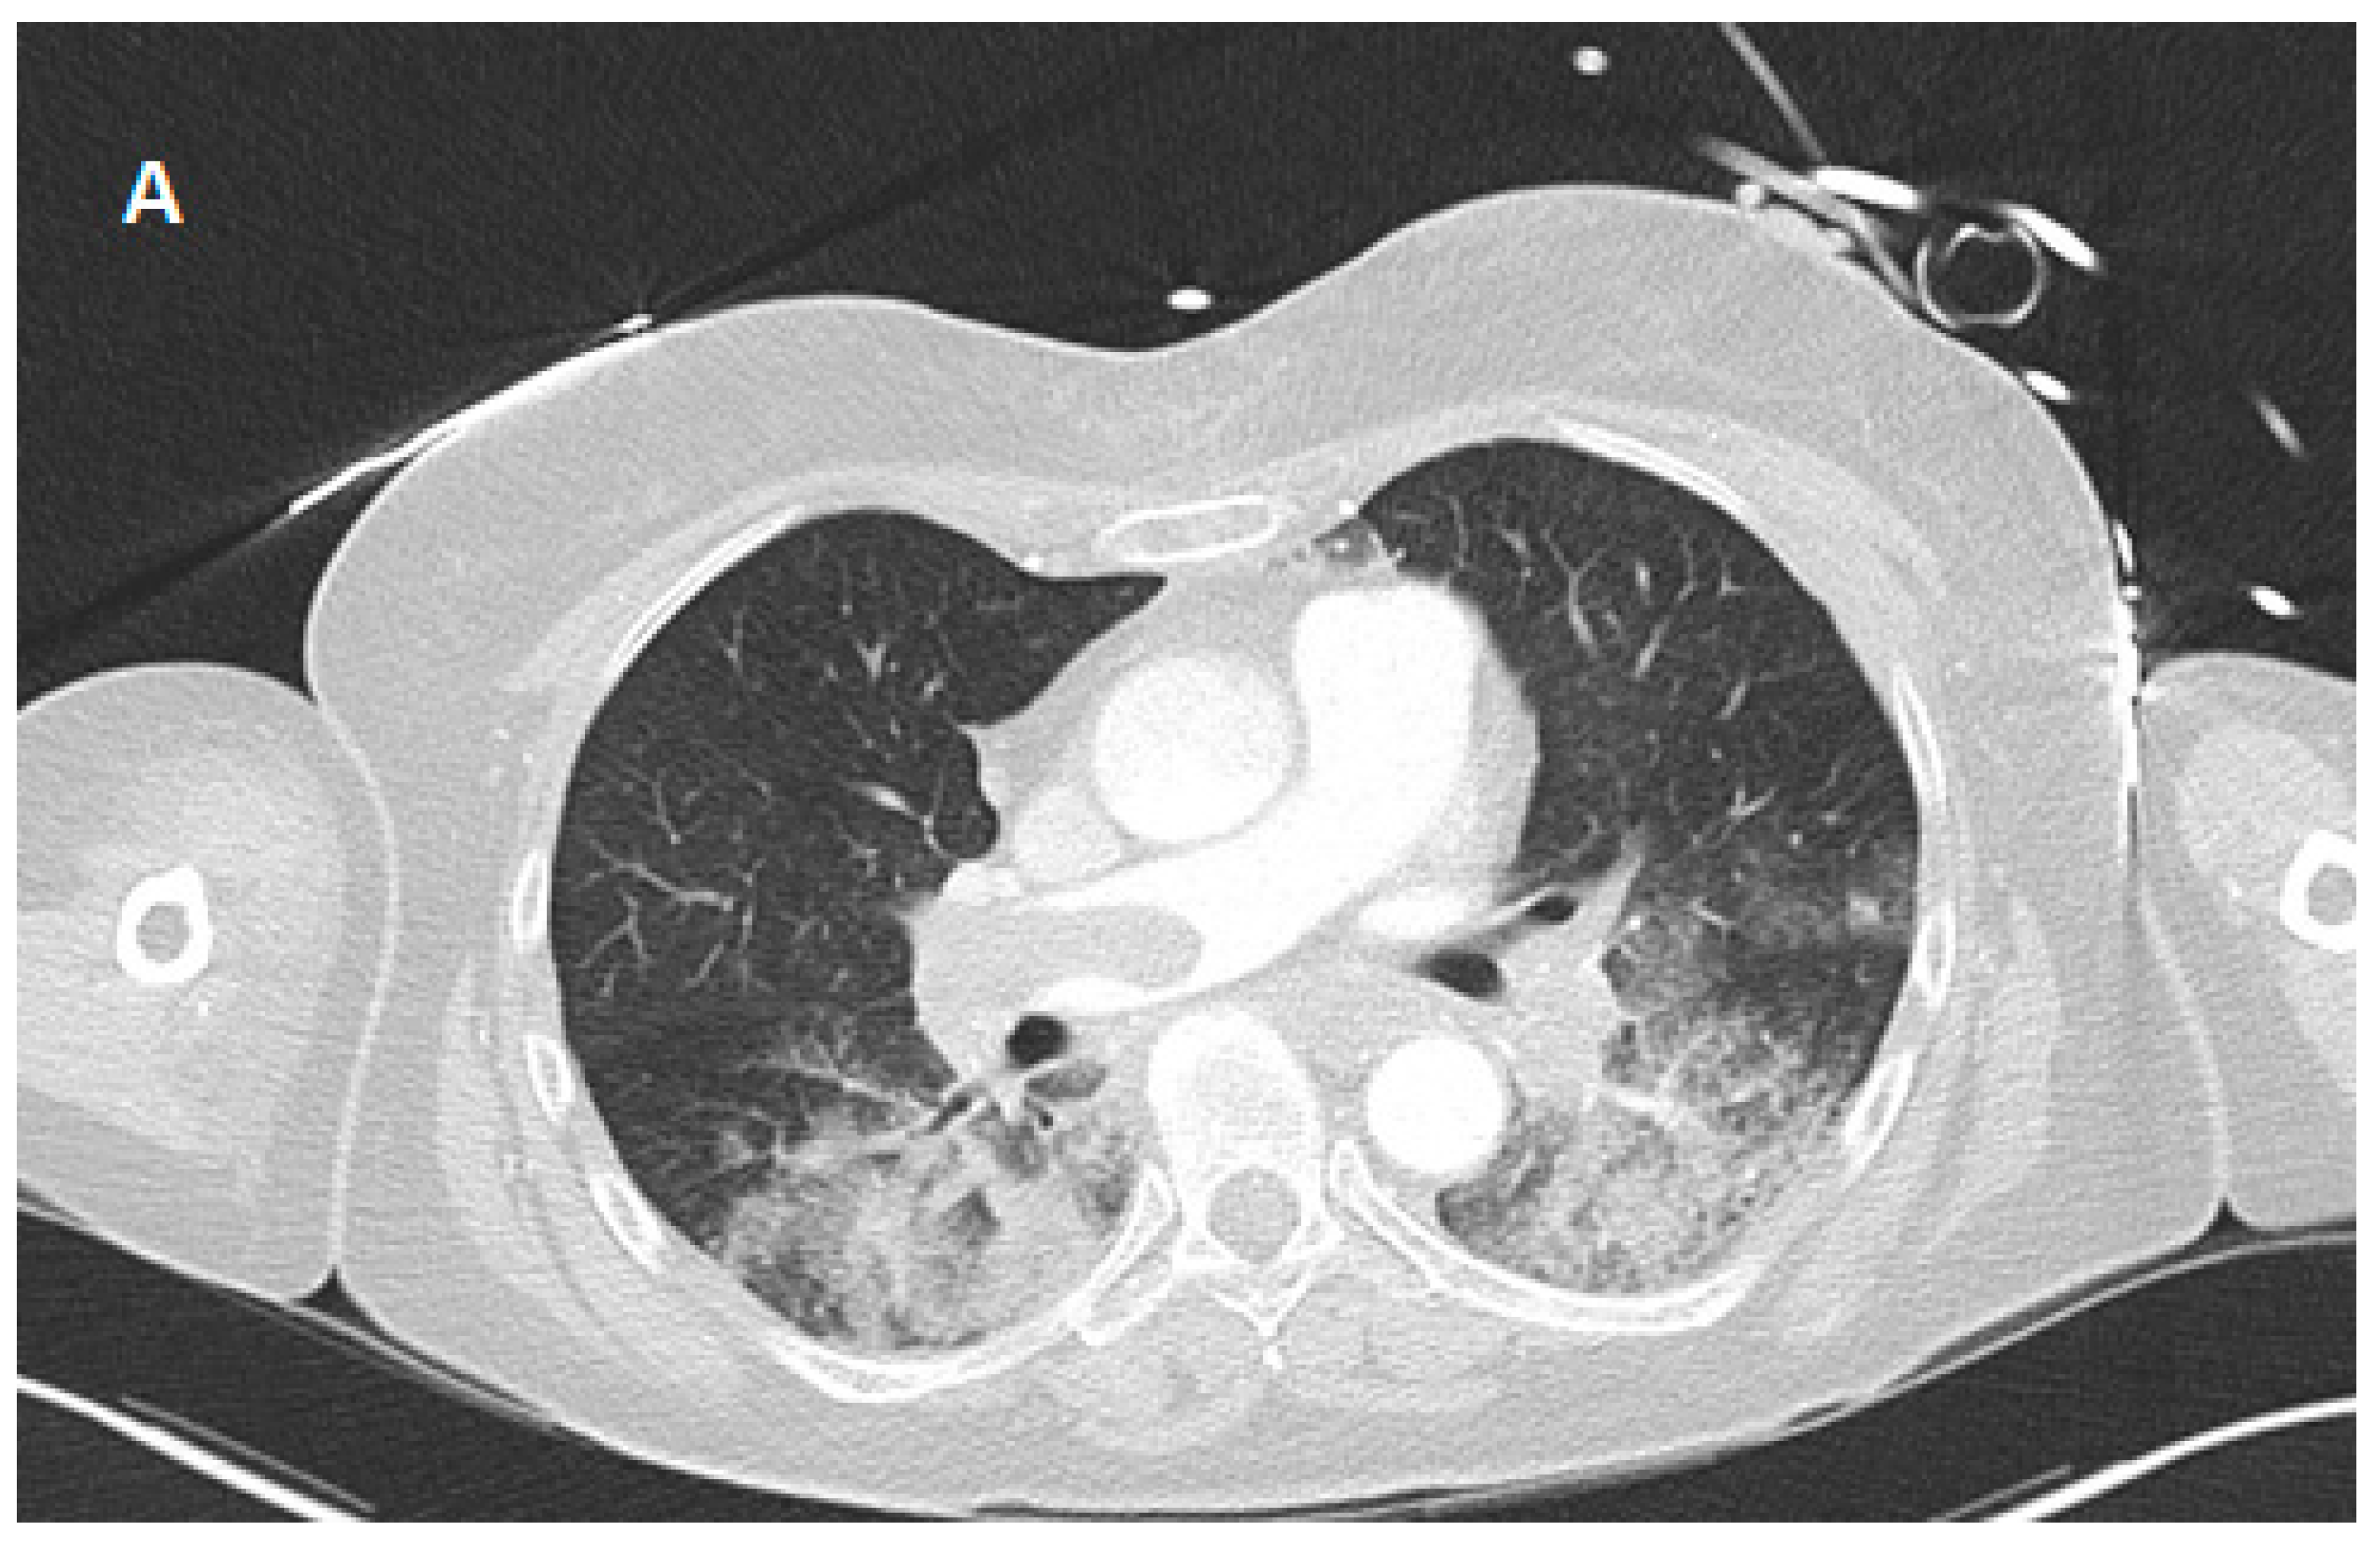

2. Case Presentation